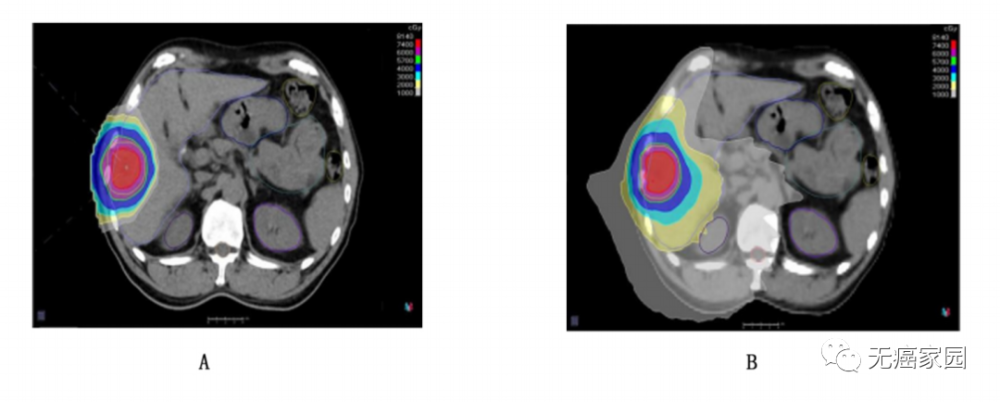

在我国一项关于12例原发性肝癌患者的回顾性分析中,研究者分别采用了质子调强放疗(IMPT)与光子螺旋断层放疗(HT)计划,对靶区及各危及器官的剂量学参数进行分析。

两种疗法的剂量分布均能满足靶区处方要求,在正常肝组织保护方面,相较于光子疗法,质子调强放疗在平均剂量上降低将近30%,且 V5~V40等指标皆取得了具有统计学意义上的肝脏保护优势。在空腔型危及器官胃、大肠、小肠、十二直肠,脊髓等方面无论最大剂量还是平均剂量水平,质子调强放疗均具有相当优势。

1例肝癌患者 IMPT 和 HT 计划的剂量分布

A:质子调强放疗;B:光子螺旋断层放疗